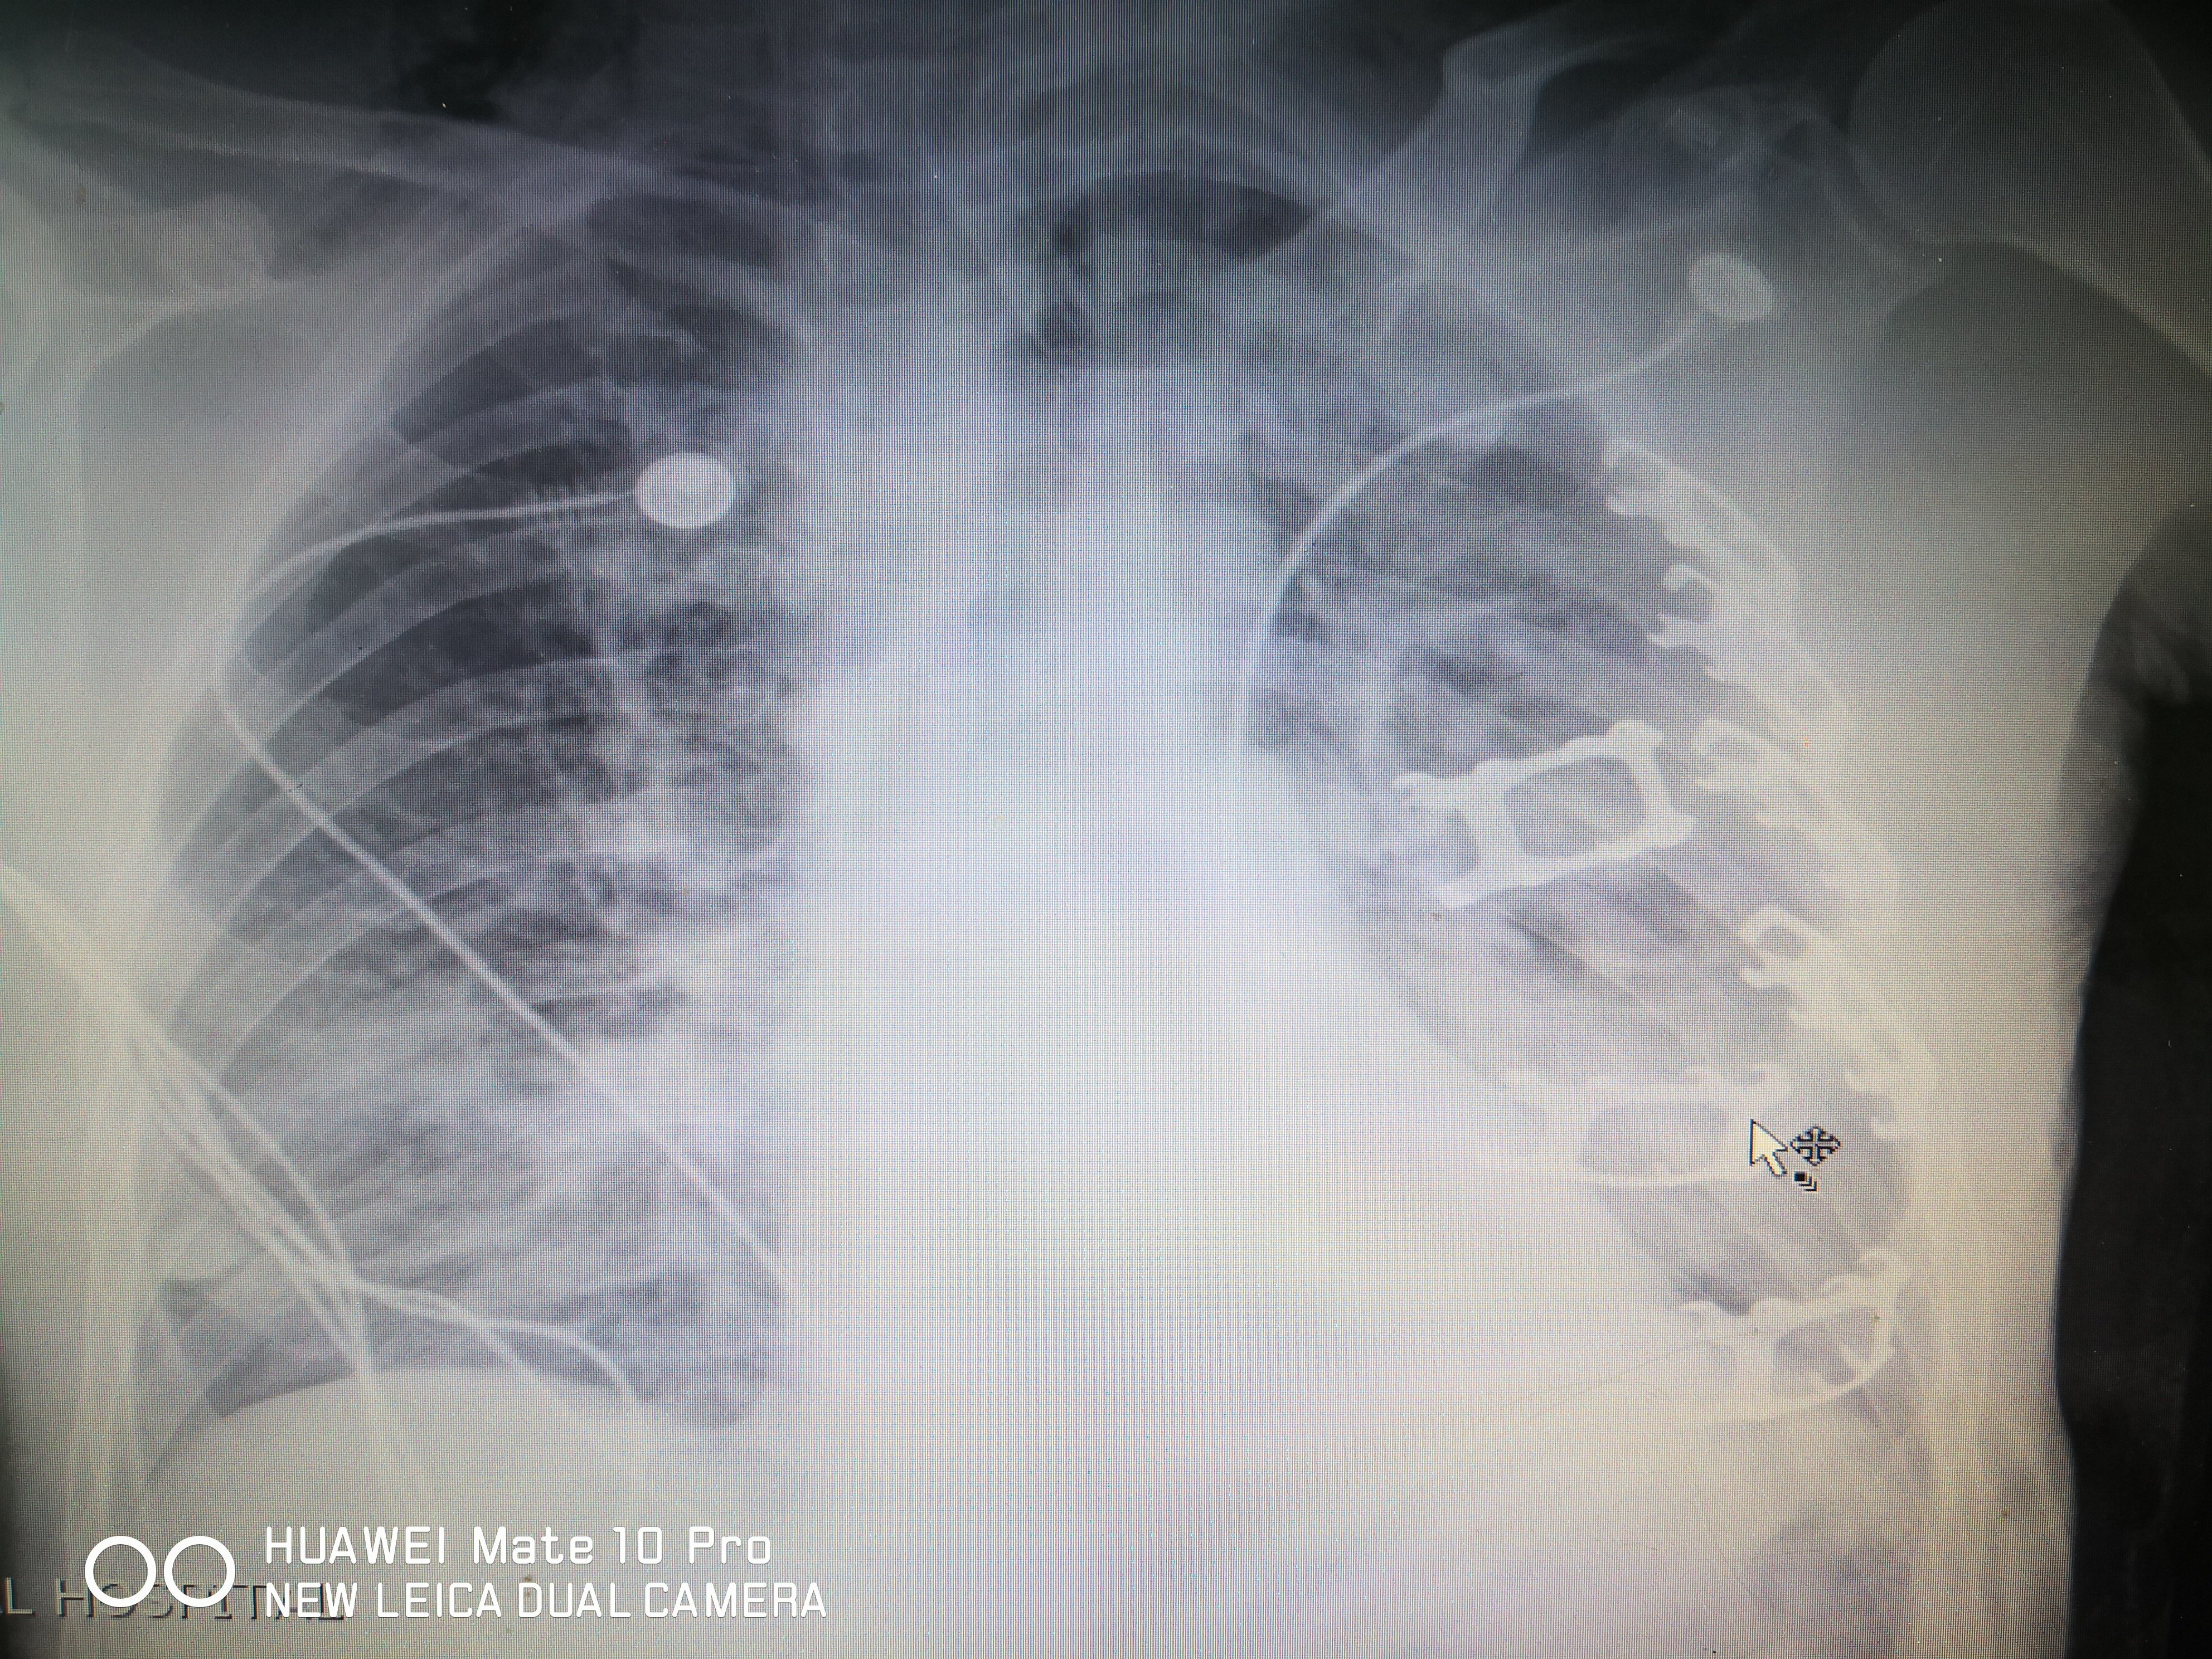

1 什麼是肋骨?肋骨共 12 對,左右對稱分佈在胸旁,與胸椎和胸骨連接形成胸廓,用來保護肺、心臟、肝臟等器官的骨骼,是整個胸腔的構架。2 肋骨骨折多發生在哪裡?肋骨的生理結構特點決定了最易折斷的部位,第 1—3 肋骨較短 胸部正位双侧肋骨未见明显错位骨折,主动脉硬化。 ct可见右侧第五前肋骨折。老年人,肺纹理粗乱,前肋靠近胸骨,重叠较多,易漏诊。 如何避免肋骨骨折的漏诊? 1询问患者有无受伤病史,车祸,摔伤,撞伤等。肋骨骨折 肋骨は左右12対の骨で背中の胸椎から前胸部の胸骨までかごのように胸腔を形成しており (図1)、その中に存在する心臓や肺ばかりでなく、腹腔内の肝臓、脾臓、腎臓の一部を保護しています。 ただ、11、12番目の肋骨の前方は胸骨にはくっついていません。 肋骨骨折は、胸部外傷の中で最も多くみられるものです。 その原因は机やタンスの角にぶつけたと

胸片可见左侧锁骨骨折,左侧第四肋骨骨皮质皱褶,易漏诊。 ct证实为左侧第二四五肋骨骨折。细微骨折,裂纹骨折,对位良好的骨折,在x片上极其容易漏诊。 病例2 女,79岁,外伤。 胸部正位双侧肋骨未见明显错位骨折,主动脉硬化。 ct可见右侧第五前肋骨折。肋骨、折リマシタ 1 下山時に転倒・強打 平成16年11月日(土曜日)、鈴鹿・入道ヶ岳の二本松尾根を降り始めるとスリップして尻餅をつきそうになった。 肋骨とは胸の内臓を覆い、胸の臓器を外力から守る役割を担っている骨です。 肋骨骨折は全骨折の 10% の割合で起き、肋骨骨折の起きやすい部位は5〜8本目の肋骨が多い傾向にありま